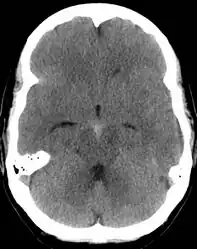

The modality of choice is computed tomography (CT scan), without contrast, of the brain. This has a high sensitivity and will correctly identify 98.7% of cases within six hours of the onset of symptoms.[28][4] A CT scan can rule out the diagnosis in someone with a normal neurological exam if done within six hours.[29] Its efficacy declines thereafter, and a lumbar puncture is also recommended.[1][4] Magnetic resonance imaging (MRI) is more sensitive than CT after several days.[5]

The Fisher Grade classifies the appearance of subarachnoid hemorrhage on CT scan.[36]